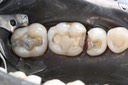

Gary Umeda #29, 30, 31 finish